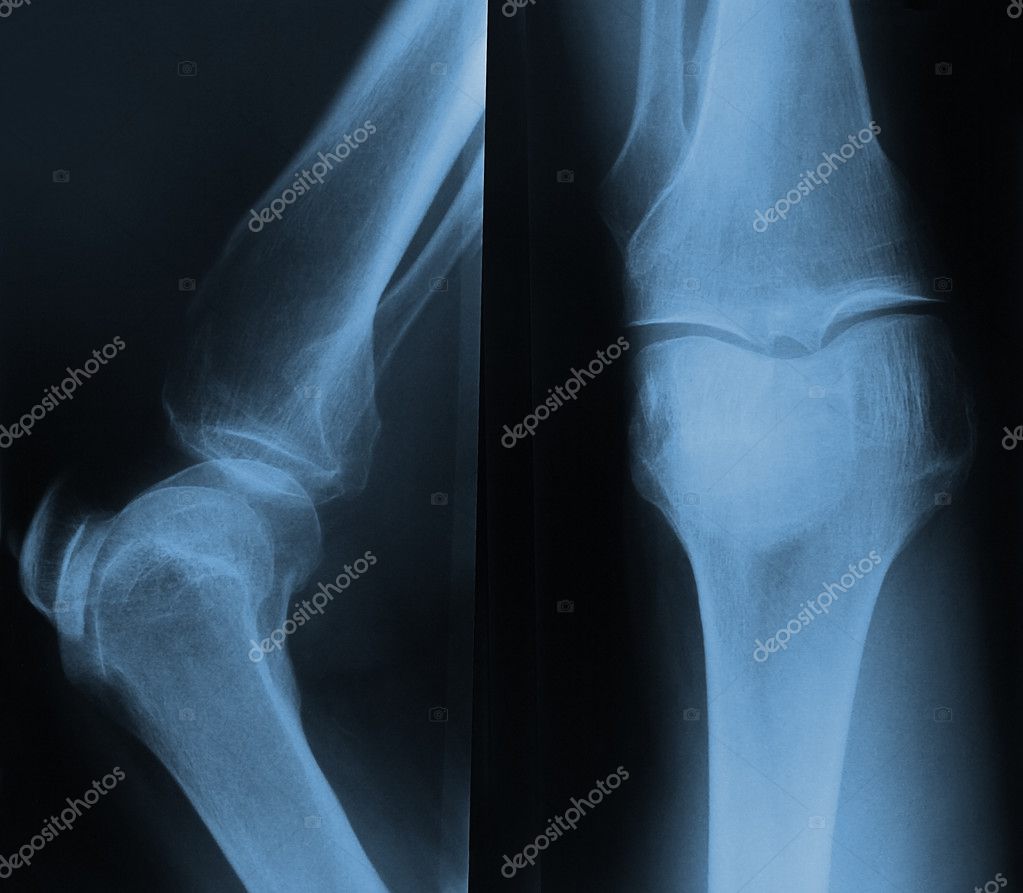

Röntgenfoto Knie Met Vocht. Poster Een röntgenfoto van een Artritis knie 60x80 cm Met een kniescan kunnen banden, pezen, kraakbeen, meniscus, bot en vochtophopingen in beeld worden gebracht. Achter het defect is het bot lichter gekleurd (botoedeem) en in de knie bevindt zich vocht (hydrops, dit is het witte vlak op de MRI).

Op deze röntgenfoto zijn de botstructuren zichtbaar van het dijbeen, het scheenbeen, het kuitbeen en de knieschijf. Achter het defect is het bot lichter gekleurd (botoedeem) en in de knie bevindt zich vocht (hydrops, dit is het witte vlak op de MRI). vocht en slijmbeurzen worden afgebeeld en kunnen afwijkingen hierin worden ontdekt